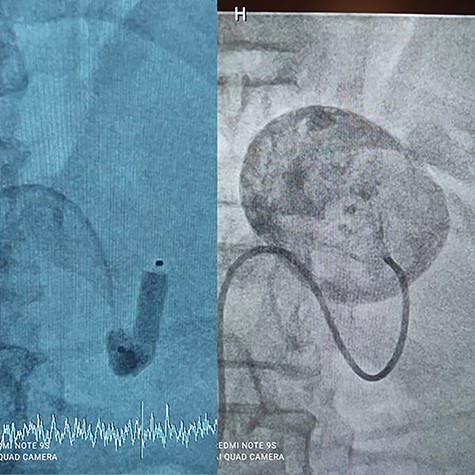

A 56-year-old male (fourth patient) evaluated for abdominal pain was referred to our hospital. In Computed tomography angiography (CTA) giant proximal SAA was diagnosed. We considered endovascular treatment. Angiography was carried out but because of arterial tortuosity wire did not pass through to the distal part of the artery. Hybrid surgery was the next plan. Balloon (7–40) expanded in proximal part of the aneurysm then in laparotomy, distal part was ligated and proximal part according to the inflated balloon was found easily (Fig. 1). After balloon was deflated, aneurysm was ligated and resected (Fig. 2).

Hybrid surgery: Aneurysm sac (Left), Angiography sheath and inflator (Right).